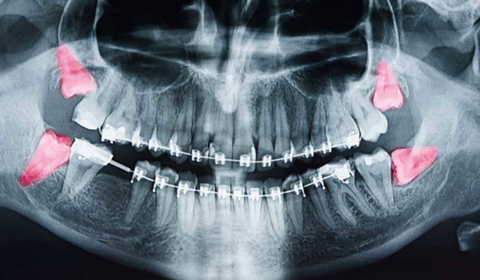

- Panoramik röntgen veya 3D tomografi ile dişin konumu ve kök yapısı incelenir

- Çene kemiği ve çevresindeki sinir yapısı analiz edilir